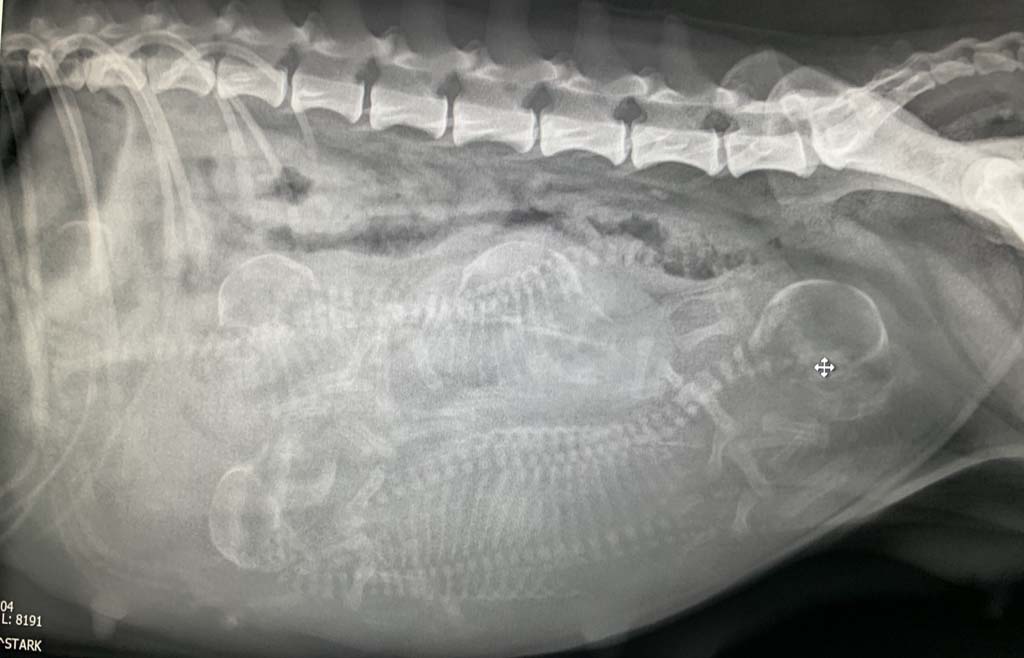

An Tag 58 haben wir uns dann davon überzeugt, dass die knapp 5Kg Gewichtszunahme nicht nur vom

Fressen kommen .....